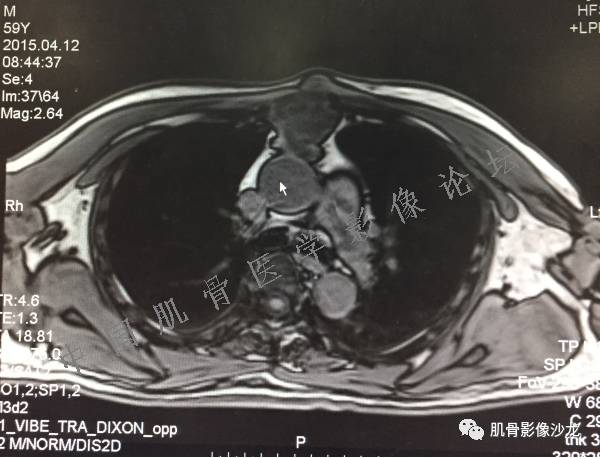

雪舞 :第二例,位于骶骨,有骨质破坏并有软组织肿块,软组织肿块边界清

雪舞: 第二例我们能够看到破坏与软组织肿块不成比例,软组织肿块大,破坏小

雪舞 :第二例挺难的,骨质破坏是溶骨性的,局部皮质中断,软组织肿块外缘光滑

医影在线: 病变无明显钙化

医影在线 :无软骨钙化